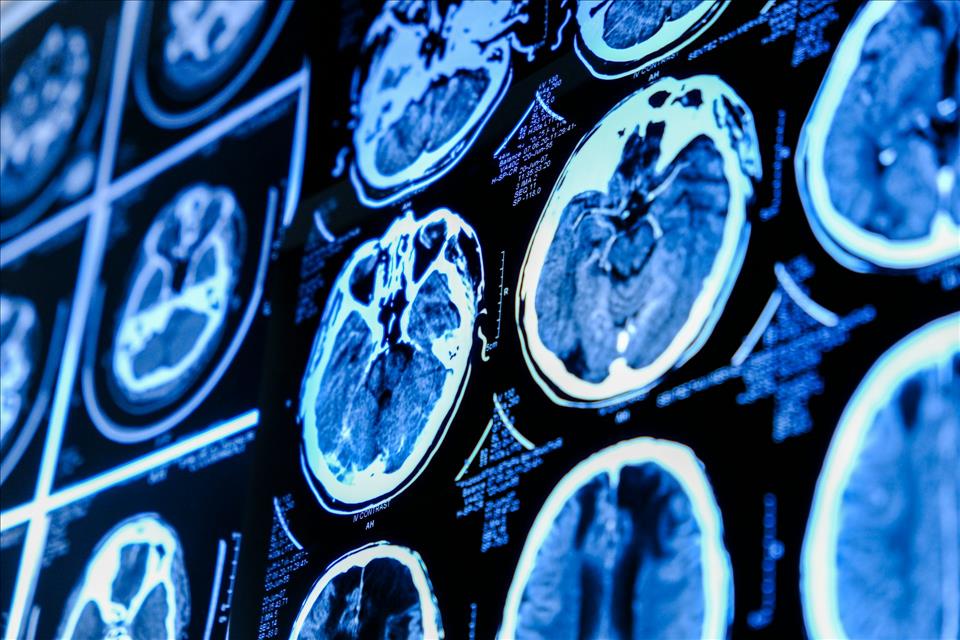

Is it always a medical emergency?About three in 100 people will have a brain aneurysm, varying in size from less than 5mm to more than 25mm in diameter. The majority are only discovered while undergoing imaging for something else (for example, head trauma), because small aneurysms may not cause any symptoms.

Surgery can repair a brain aneurysm, and stop it from rupturing. Roman Zaiets/Shutterstock Surgery can prevent a rupture